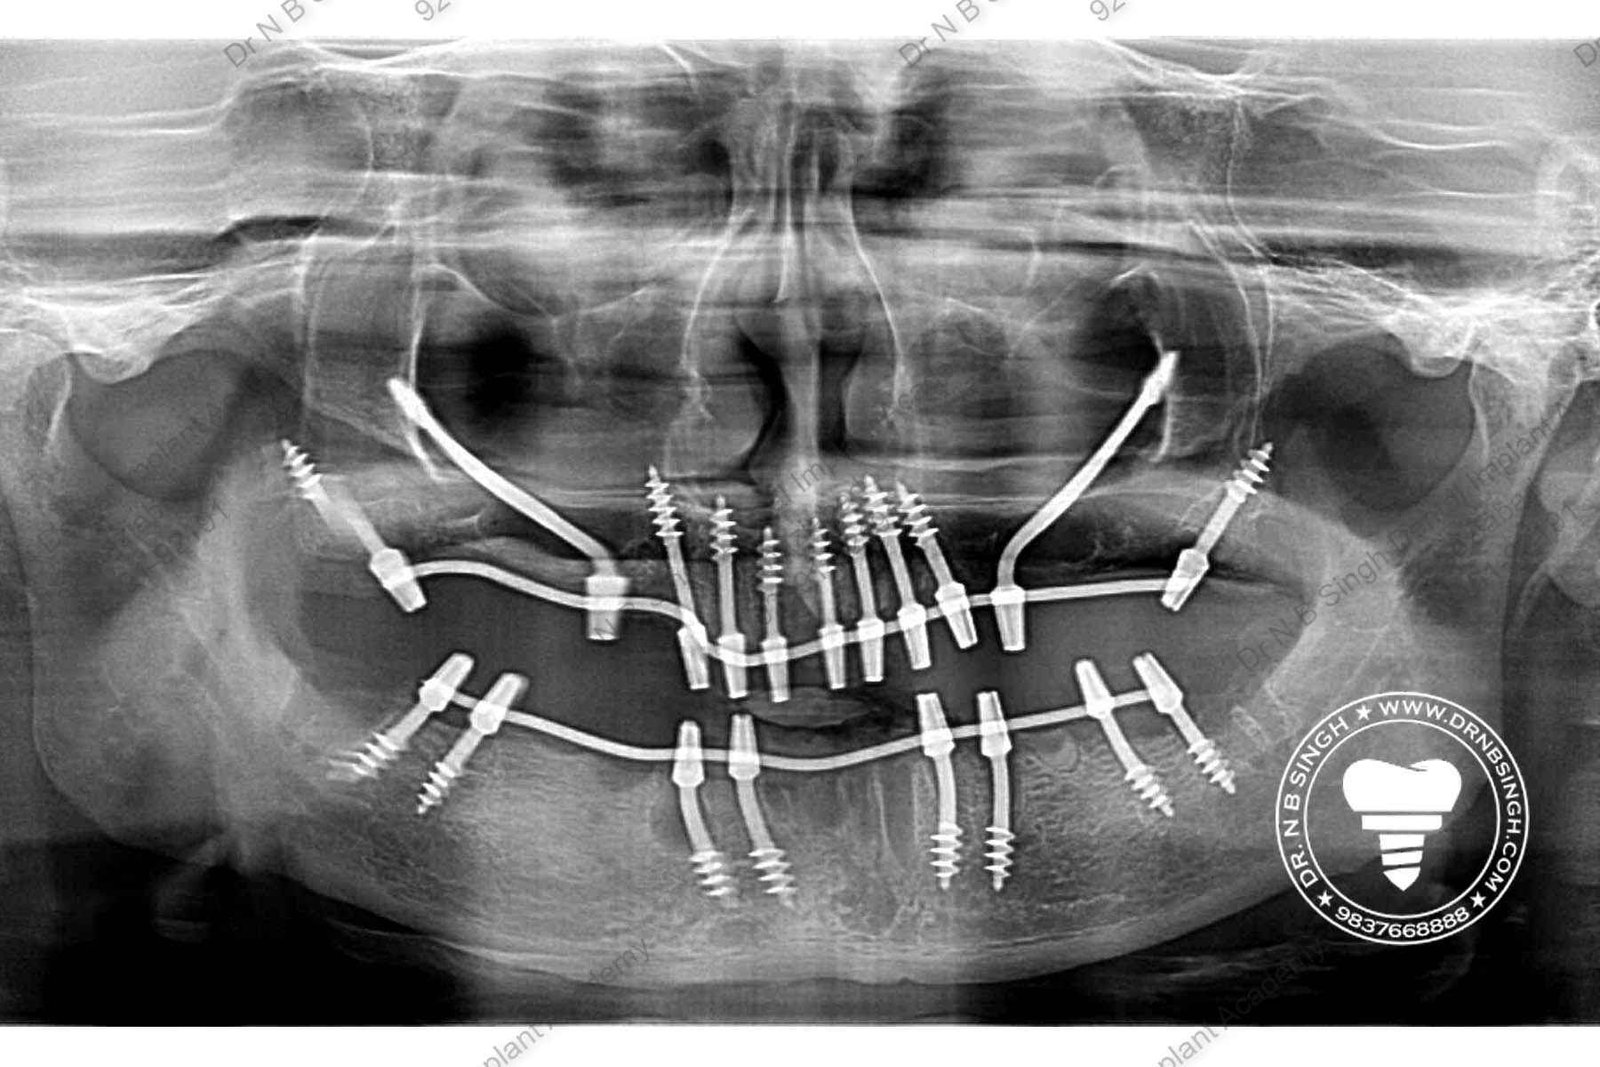

C1005 zygomatic basal implant full mouth – Ali Hasan 4

Dr. N.B. Singh